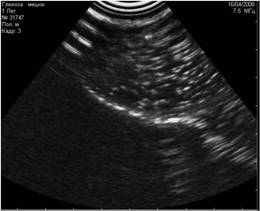

Рис. 14. Режущие тени от кривизны капсулы почки. |